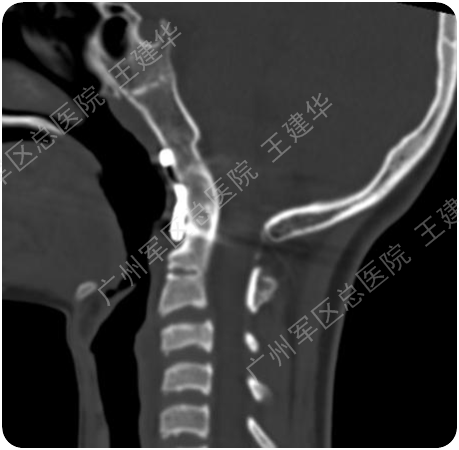

三维CT显示患者合并寰枕融合及C2/3融合,颅底凹陷

本例患者手术过程

手术前后对比

手术后2年复查的CT,显示侧块关节已经完全融合